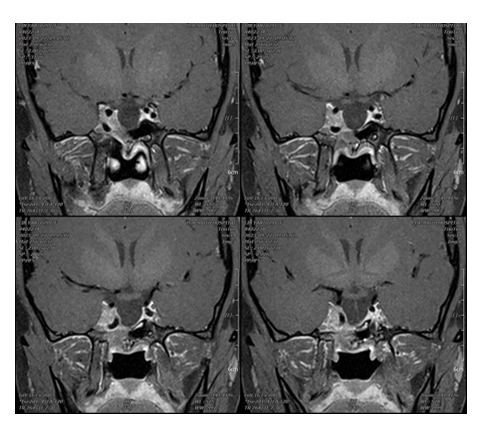

术前MRI示垂体大腺瘤,侵袭右侧海绵窦,侵袭蝶窦。KnospIV级。术前激素水平检查示OGTT-GH >40 ng/mL。彩超检查示结节性甲状腺肿;心包少量积液。

患者于2017年3月接受经鼻蝶入路垂体腺瘤切除术,术中见肿瘤呈灰白色,质地较软,血供不丰富。术后第2天行垂体MRI增强扫描,提示右侧海绵窦内仍有肿瘤残留。术后病理诊断为生长激素型垂体腺瘤,Ki-67指数为8%。术后OGTT-GH为8.73 ng/mL。

术后2个月起开始使用长效生长抑素类似物治疗。2020年7月,在北京某大型三甲医院再次行内镜下经蝶手术,因术中解剖困难,颈内动脉阻挡导致未能成功切除肿瘤。

2021年4月开始接受伽马刀治疗,至2021年7月出现小腹膨隆,发现意外妊娠。2021年6月进行最后一次产前用药,产后恢复SSA治疗,OGTT-GH谷值为8.99 ng/mL,IGF-1控制在参考范围内(16-356 ng/mL)。自2017年3月至2022年9月,ACTH、皮质醇、FT4等指标波动均在正常范围。

目前患者仍规律使用SSA维持治疗,2024年1月复查内分泌功能示FT4为14.03 pmol/L,ACTH为19.3 pg/mL,皮质醇为12.42 μg/dL,提示腺垂体功能正常。2025年5月随访结果显示IGF-1为175 ng/mL(参考范围:71-234 ng/mL),随机GH为6.23 ng/mL。

图:近期随访结果。患者规律使用SSA治疗,IGF-1 175 ng/ml,随机GH 6.23 ng/ml。